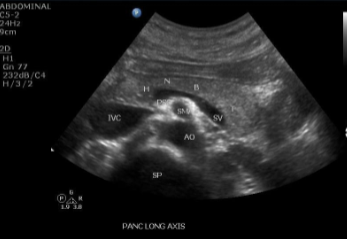

Neck/Body- SV, SMA, AO, Wirsung’s duct

Sag Pancreas whole

transverse position w head neck body